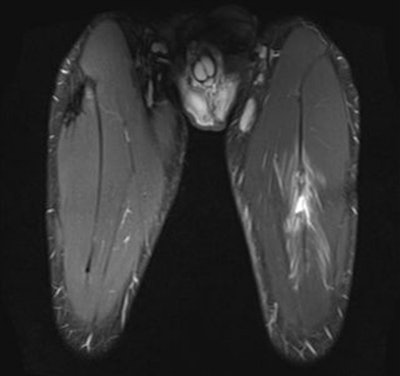

the musculotendinous junction. Note the feathery edema pattern within the muscle radiating from the primary injury site. Below: Extended field-of-view ultrasound demonstrates loculated hematoma at the musculotendinous junction with surrounding increased reflectivity within the rectus femoris muscle. All images courtesy of Dr. Justin Lee, Chelsea and Westminster Hospital.

MRI is the modality of choice in many football injuries (see figure). For grade I muscle injuries, it can detect abnormalities to the biceps femoris and myotendinous junction. In acute cases, there is a slight increase in signal on T1-weighted images, and a "feather-like" increased signal can be seen on T2/short tau inversion recovery (STIR), but there is no architectural distortion.

Along with Lee and his Chelsea and Westminster colleague Dr. Jerry Healy, Dr. Jan Ekstrand, an orthopedic surgeon who runs the medical division of the Union of European Football Associations (UEFA), organized a study in the 2007-2008 Champions League season that looked at muscle injuries to thighs. Included in the study were Chelsea, Arsenal, Inter Milan, PSV Eindhoven, FC Shakhtar Donetsk (Ukraine), and FC Porto. A total of 303 injuries were recorded by the 18 participating teams, and hamstrings were affected in 184 cases (61%) and the quadriceps in 119 players (39%).